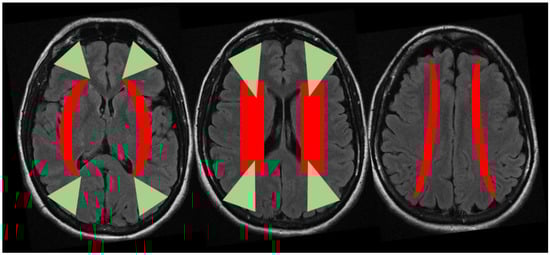

4. Discussion

We report three patients with stroke as presenting symptom of hypereosinophilia from three different causes, two of them fulfilling the criteria for HES [1]. The pathophysiological mechanisms of stroke in the context of hypereosinophilia may produce a composite pattern on neuroimaging studies, ranging from a large vessel occlusion (or territorial) pattern [8] to multiple scattered lesions in several different vascular territories, and in particular in border zones [5,6,9,10]. These last ones may be considered a hallmark of HES-related stroke, in particular without evidence of hemodynamic unfavorable conditions, being caused by a direct toxic effect of the increased number of circulating eosinophils to the endothelium of small cerebral vessels. Border zone infarcts are ischemic lesions that are localized at the borders of the distal fields of two non-anastomosing arterial systems [11,12,13]. These lesions are approximately 10% of all brain infarcts and, although their pathophysiology is yet a matter of discussion, the more accepted hypothesis is that decreased (or misery) perfusion in the distal regions of the vascular territories leaves them vulnerable to infarction because of the end-type arterioles without an efficient anastomotic network among superficial and deep territories (e.g., in middle cerebral artery—MCA—supply) or MCA to posterior cerebral artery/anterior cerebral artery (PCA/ACA) and PCA to ACA borders [13,14], as demonstrated in an autoptic study [15]. Traditionally, two types of border zone infarcts are identifiable according to their location: external (or cortical) and internal (or subcortical) type [13], as detailed in Figure 4.

The anterior external border zone infarcts are more common than posterior ones because of the high prevalence of ICA disease. Indeed, posterior external border zones infarctions require vertebrobasilar disease with superimposed fetal-type PCA. Among internal border zones infarcts the most common location is on the lenticulostriate–MCA border zone, supplied by the end branches of deep perforating lenticulostriate arteries and medullary penetrators from the pial–MCA. The putative external and internal border zones are superimposed on axial brain MRI images in the Figure 5. However, it is important to consider that the extension and localization of the border zones can undergo variations in single individuals both in normal conditions and in situations that create chronic hemodynamic impairment. Moreover, the anatomical and functional organization of white matter vasculature may take account of different patterns of border zones, accordingly to a centripetal/centrifugal or interconnected organization [16].

Another relevant issue is that external and internal border zone infarcts may have a different pathogenesis, which may be inferred by neuroimaging appearance. As shown in Figure 5 (green triangles), external border zone infarcts usually are wedge-shaped and their hemodynamic origin is hard to define only on the neuroimaging basis because of the wide variability of arterial territories and leptomeningeal collaterals. Therefore, isolated external border zone infarctions may be embolic rather than purely hemodynamic and they may be associated to small cortical infarcts. The cause of unilateral posterior external border zone infarcts is more often embolic than hemodynamic; on the contrary, bilateral infarcts are more likely to be caused by underlying hemodynamic impairment [21]. Instead, internal border zone infarcts are usually multiple and occur in a rosary-like pattern (as seen in Figure 2 for the second patient we described). A unique widely shared definition of this pattern does not exist; it has been assumed from one of the first reports that the rosary-like pattern is a series of three or more lesions, each with a diameter of 3 mm or more, arranged in a linear pattern parallel to the lateral ventricle in the centrum semiovale or corona radiata [22]. Internal border zone infarcts are also categorized as partial or confluent [12]; partial infarcts are large, elongated (cigar shaped), and arranged in a line parallel and adjacent to the lateral ventricle, looking like the beads of a rosary. It has been postulated that the duration of hemodynamic impairment is related to a partial o confluent appearance, respectively with a shorter and longer lasting impairment [23]. The main neuroimaging differential diagnosis of internal border zone infarcts is represented by superficial perforator (medullary) infarcts, caused by caused by the occlusion of medullary arteries arising from pial plexuses, because of the similar appearance on MRI. Usually they are smaller, more superficially located and widely scattered than internal border zone infarcts and they have a tendence to spare the paraventricular regions, more typically affected in internal border zone infarcts. The hemodynamic factor is much more evident in internal border zone infarcts than in external border zone infarcts, mainly because the greater vulnerability of the internal border zone due to anatomical feature of the supplying arterioles. Indeed, internal border zones are supplied by medullary penetrating vessels branching from MCA and ACA and by deep perforating lenticulostriate branches. The first ones are the most distal internal carotid artery (ICA) branches with the lowest perfusion pressure. The second ones have poor collateral supply, and unfortunately, there are no anastomoses between the deep perforators and the white matter medullary arterioles [16]. The consequence of this anatomical organization of the cerebral vasculature is that the centrum semiovale and corona radiata are more susceptible than other brain regions to hemodynamic-related ischemia. Conversely, the external border zone is closer to the cortical surface, where shorter penetrating arteries originate, and it has a better chance of developing a collateral supply through leptomeningeal or dural anastomoses [13,16]. The higher probability of hemodynamic impairment may be predicted when external and internal border zone infarctions co-occur. Although more known in the supratentorial compartments, there is a corresponding border zones organization in the cerebellum. Border zone infarcts in the cerebellum are usually less than 2 cm in size and are located at the borders of the anterior inferior cerebellar artery (AICA), superior cerebellar artery (SCA), posterior inferior cerebellar artery (PICA), and their branches. The pathophysiology of cerebellar border zones infarctions is similar to the one of supratentorial border zone infarctions, combining the hemodynamic and embolic hypotheses. As expected, small border zone lesions may coexist with large territorial infarctions. The bilateral cerebellar infarcts shown in Figure 3 for the third patient may have a predominantly hemodynamic (border zone between lateral and medial branches of PICA o both sides) than embolic pattern, whereas supratentorial infarctions in the same patient have a clear territorial pattern.

Figure 5. Putative location of the external (green) and internal (red) border zones superimposed on three sequential axial slices of brain MRI (FLAIR sequence). Abbreviations: FLAIR: Fluid Attenuated Inversion Recovery.